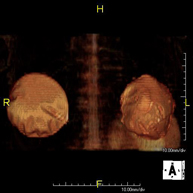

Prova diagnòstica no invasiva que consisteix en l'obtenció d'imatges d'alta definició anatòmica del fetge mitjançant l'ús d'un camp electromagnètic i ones de ràdio (amb un emissor i un receptor). No utilitza radiació ionitzant. Es realitza per estudiar qualsevol lesió localitzada en el fetge. Normalment es requereix l'ús de contrast paramagnètic (Gadolini) per caracteritzar les lesions. És necessari realitzat la prova en dejú (6 hores). - RM de Ronyons

Prova diagnòstica no invasiva que consisteix en l'obtenció d'imatges d'alta definició anatòmica d'ambdós ronyons mitjançant l'ús d'un camp electromagnètic i ones de ràdio (amb un emissor i un receptor). No utilitza radiació ionitzant. Es realitza per estudiar qualsevol lesió localitzada en ambdós ronyons. Normalment es requereix l'ús de contrast paramagnètic (Gadolini) per caracteritzar les lesions. - RM de Glàndules Suprarenals